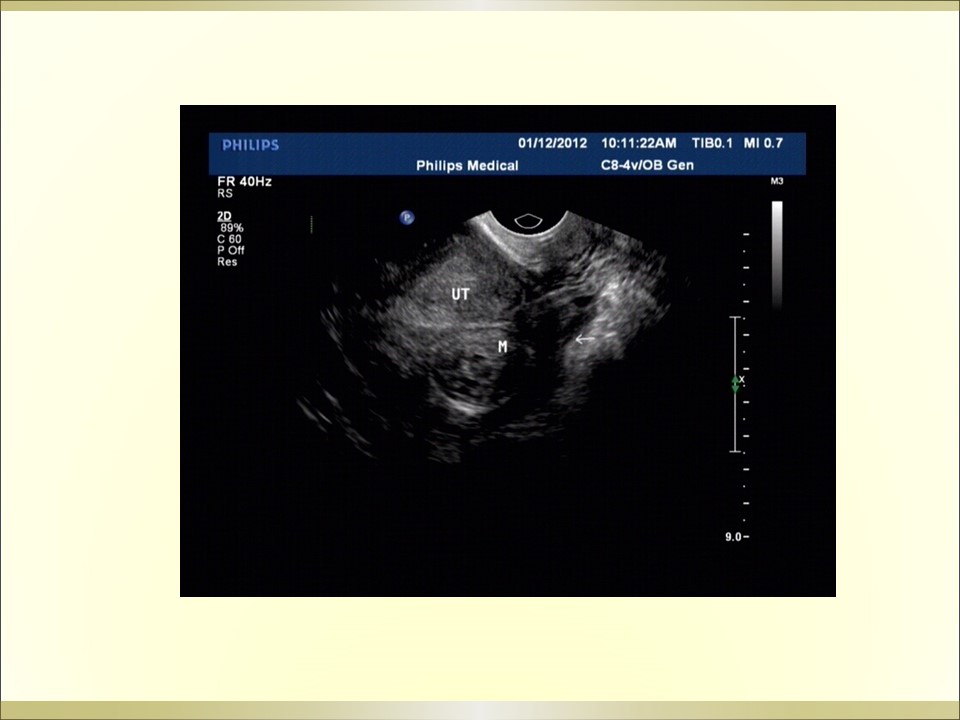

妇产科急腹症是指因妇科疾病引起的剧烈的急性腹痛,可以是原有疼痛突然加剧,或原无疼痛突然发生,是病因较多的常见病,特点是发病急、病变进展快、病情重,需要及时作出病因诊断及治疗。